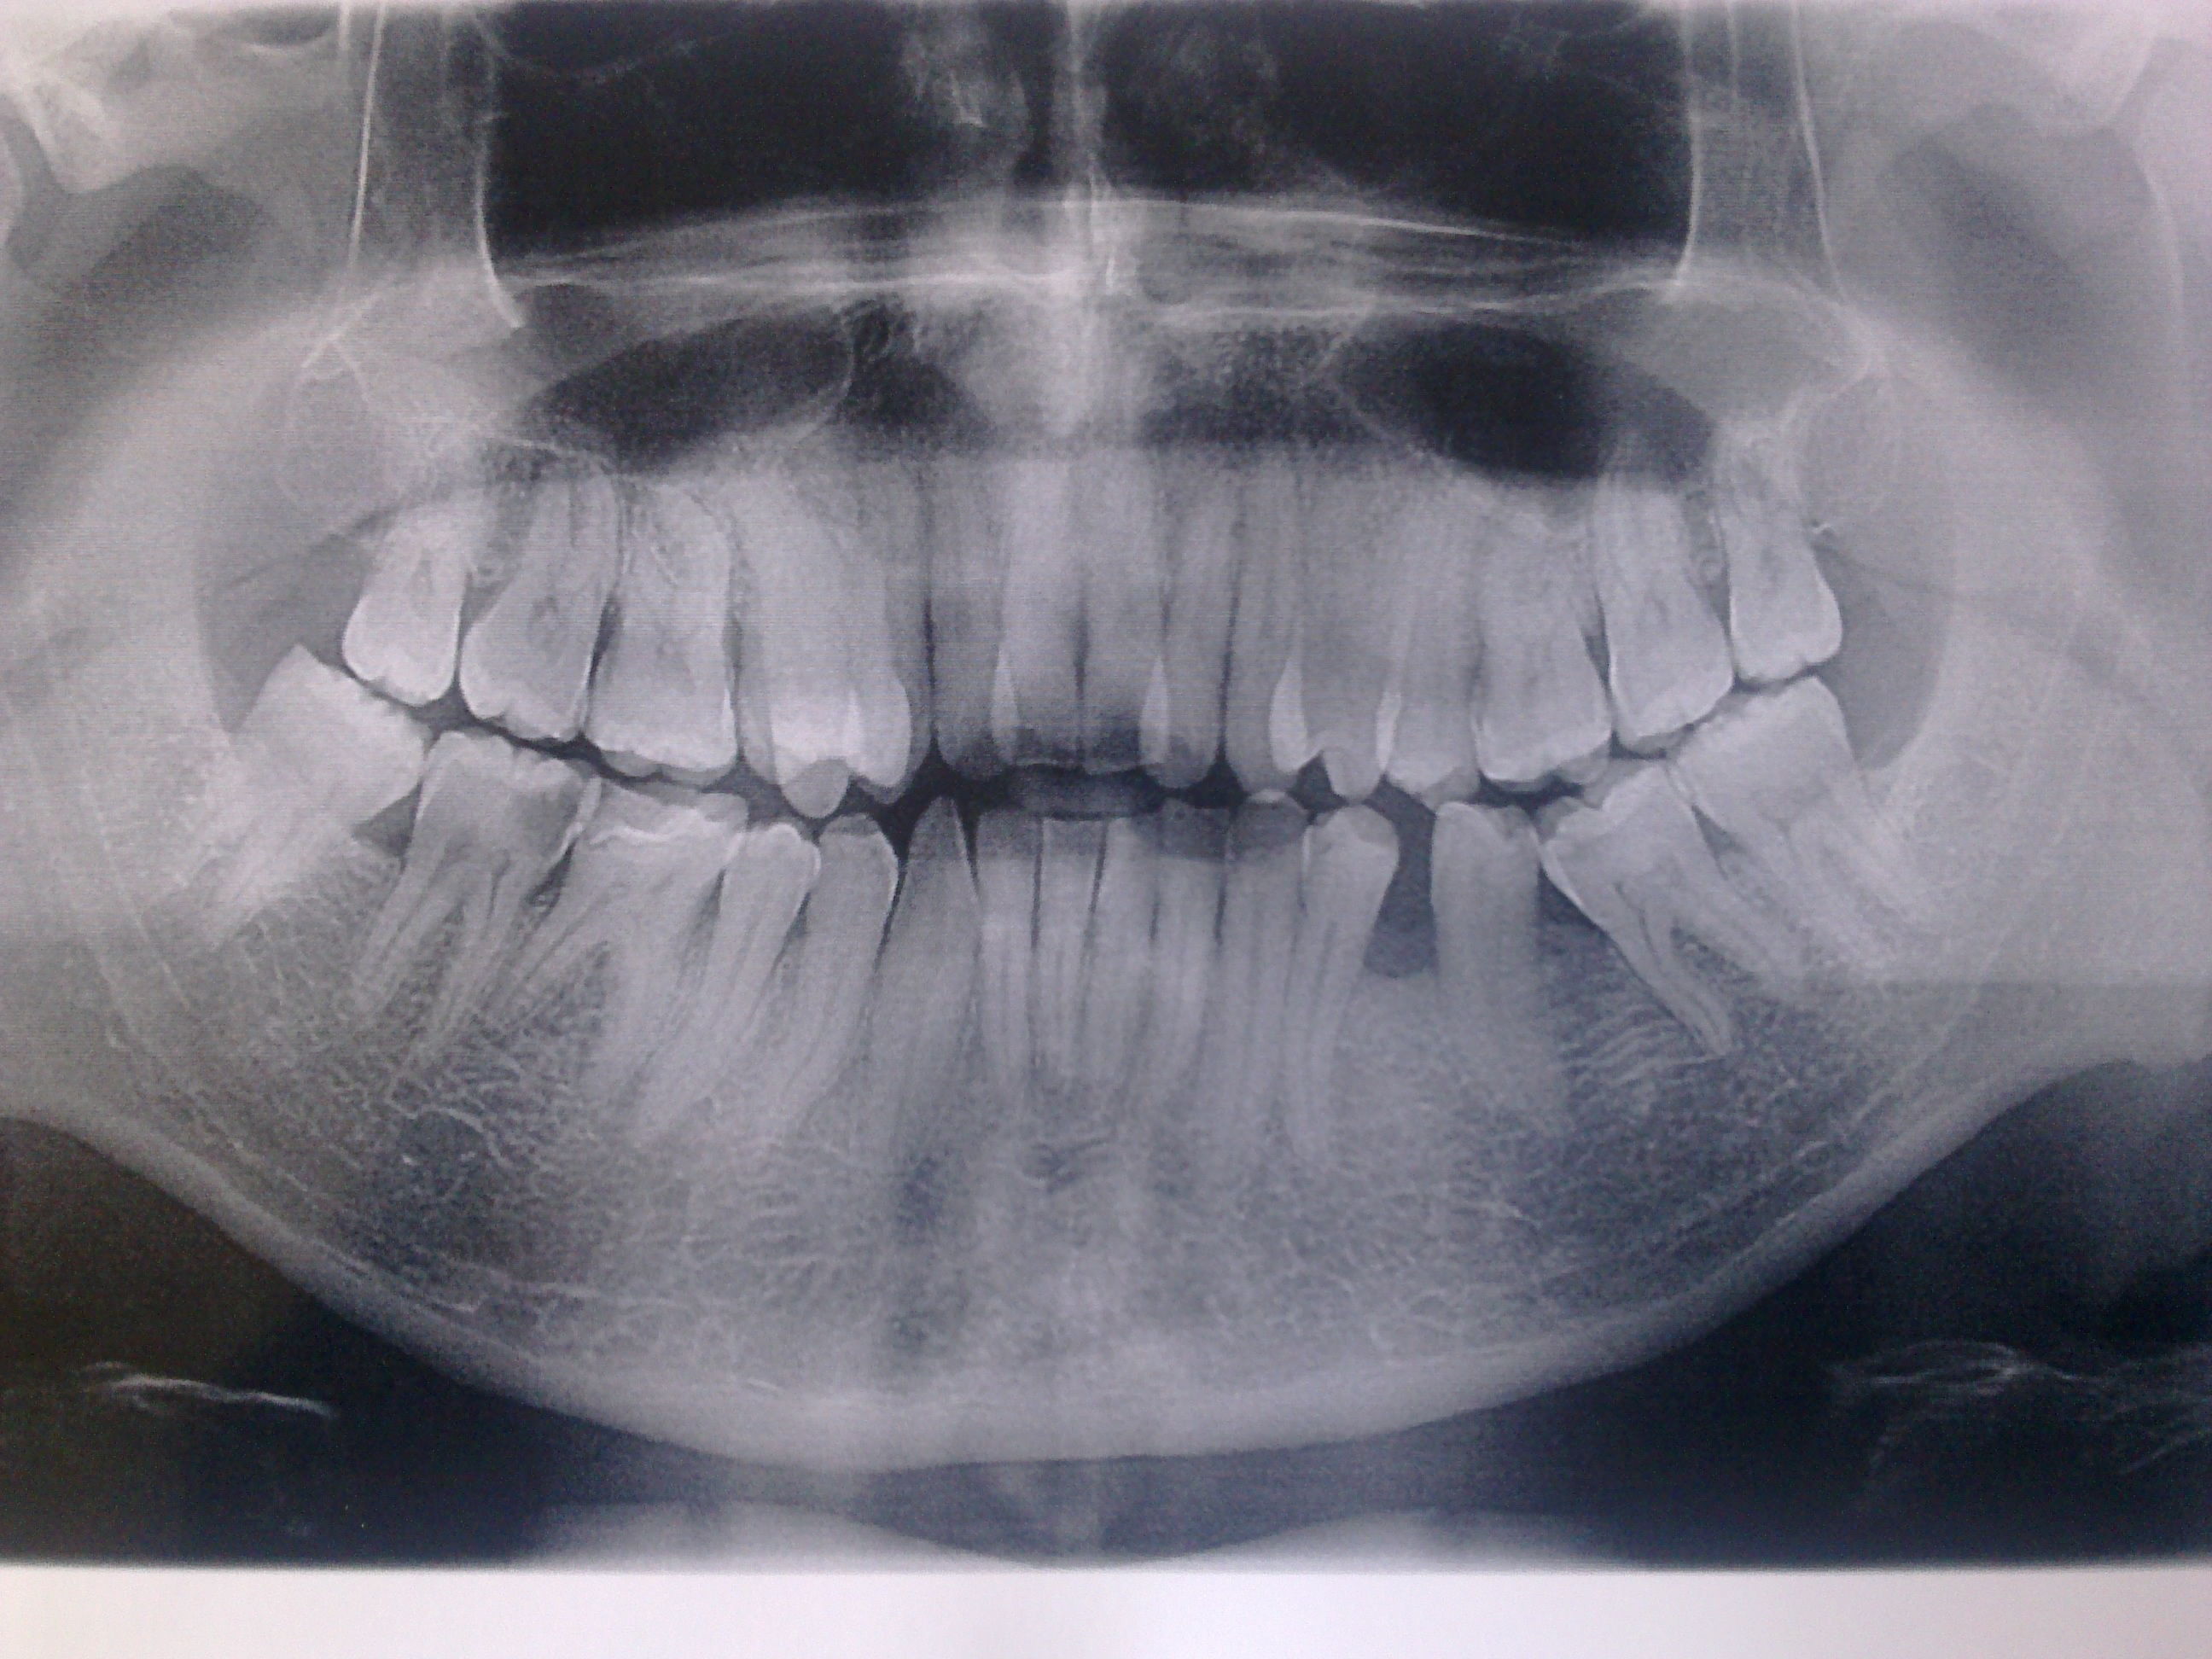

Здравствуйте уважаемый доктор! Прокомментируйте пожалуйста "ситуацию во рту". Снимок прилагаю, что необходимо пролечить, какого рода необходимо лечение? Т.е. кариес, пульпит и т.д. В верхнем ряду справа 4-ый зуб растет чуть "внутри" остальной линии зубов, но это вроде не сильно беспокоит. Больше беспокоят не сильные тянущие боли справа снизу, при чем непонятно от какого именно зуба. Во втором дырка, его понятно, что нужно лечить, в третьем справа — пломба, поставленная порядка 10-ти лет назад, но какой ноет непонятно... Заранее благодарю за ваши рекомендации.

Данный снимок не совсем информативный и к тому же для корректной консультации также необходим очный осмотр. Запишитесь ко мне на бесплатный прием по тел: +7 (495) 778-47-45, и я вам все подробно расскажу. Сейчас что бы я не делал, однозначный диагноз не поставить. Ноет, скорее всего, зуб с дыркой, прогрессирует периодонтит (хроническое воспаление) . Больше ничего сказать к сожалению не могу, попросту не вижу и не уверен.